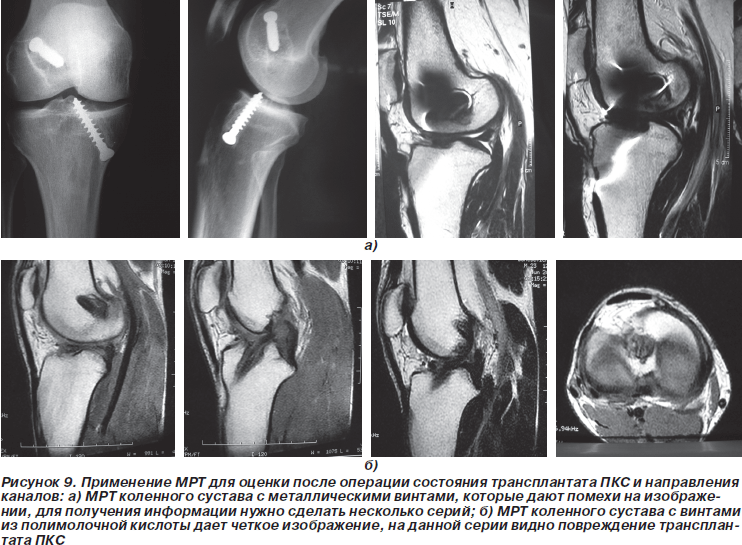

Отличные результаты удалось получить при оценке состояния трансплантата после пластики ПКС. Контрольная МРТ оказалась отличным методом, позволяющим оценить позицию каналов, направление и целостность трансплантата. Если не применялись металлические фиксаторы, то удавалось получить полную информацию. При использовании титановых винтов изображения были искажены, тем не менее имелась возможность получить срезы, по которым можно сделать выводы о состоятельности трансплантата и позиции каналов.